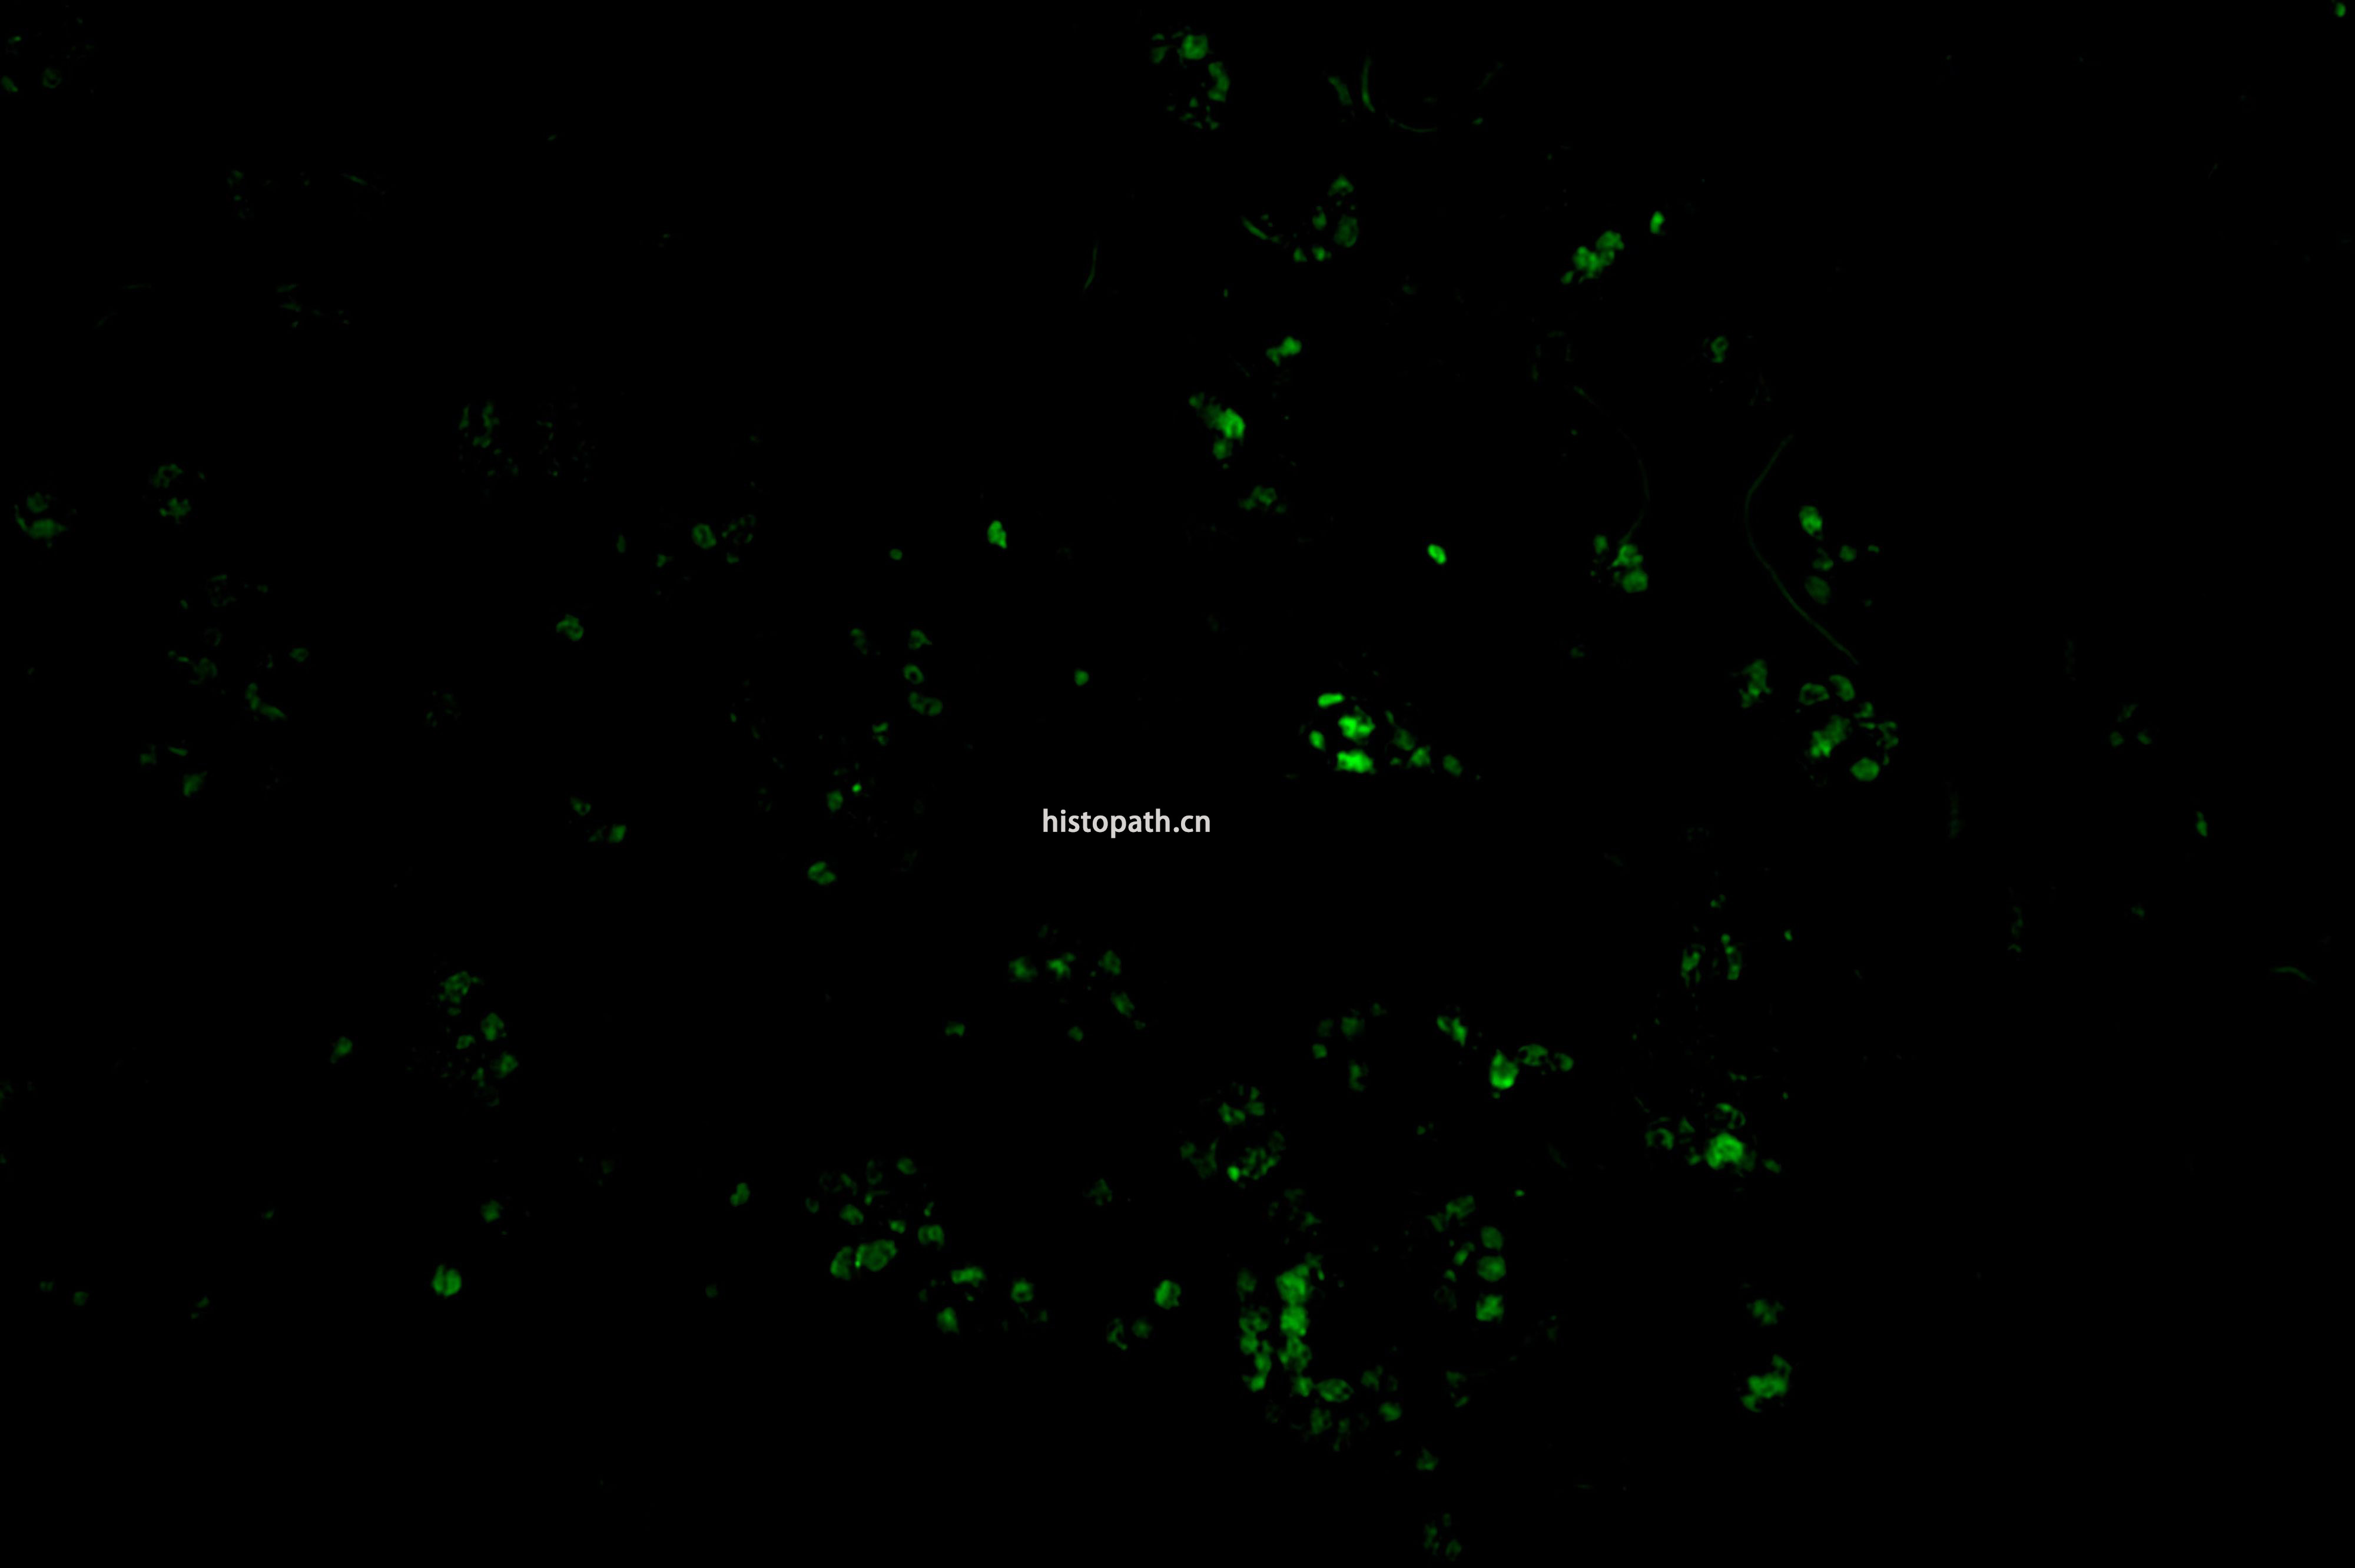

TUNEL染色荧光法

TUNEL检测原理:

细胞在发生凋亡时,会激活一些DNA内切酶,这些内切酶会切断核小体间的基因组DNA。细胞凋亡时抽提DNA进行电泳检测,可以发现180-200bp的DNA  ladder。基因组DN A断裂时,暴露的3'-OH可以在末端脱氧核苷酸转移酶(Terminal Deoxynucleotidyl TransferaseTT)的催化下加上绿色荧光探针荧光素(FITC)标记的dUTP(fluorescein-dUTP),从而可以通过荧光显微镜或流式细胞仪进行检测,这就是TUNEL(T dT-mediated dUTP Nick-End Labeling)法检测细胞凋亡的原理。